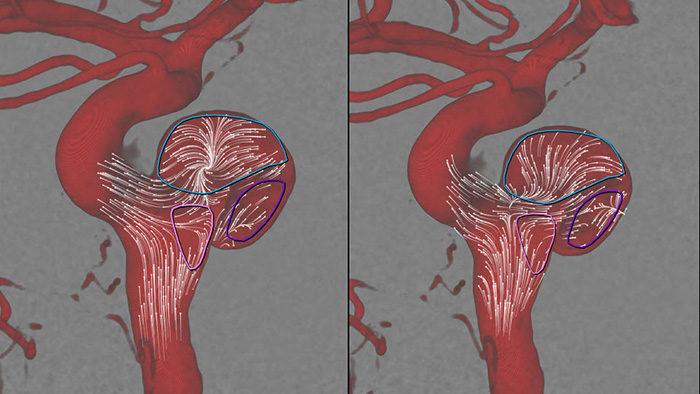

Усовершенствованная технология Roadmap Pro способствует улучшению визуализации перекрывающихся сосудов, сохраняя при этом баланс дозовой нагрузки. Во время установки спирали для эмболизации данное приложение можно настроить для наблюдения за продвижением.

SmartCT Angio за несколько секунд предоставляет объемные данные для просмотра и проведения оценки местоположения, размера, шейки аневризмы и тяжести состояния больного. 3D-объемные изображения визуализируются с высоким пространственным разрешением и автоматической компенсацией движений пациента.